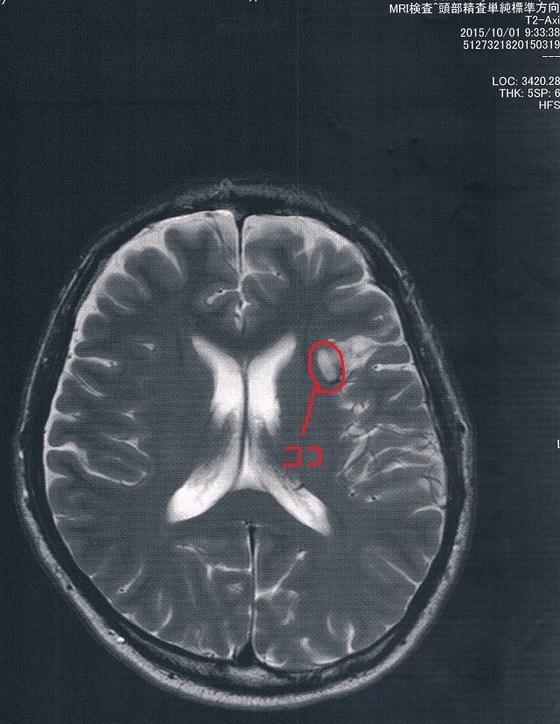

MRI検査の結果、半年前と比べて変化は無し!

目に見えるような進行は無いということだ! やったね!

当然、一番心配だった悪性転化もしていない。

2015/10/1(手術後16か月)のMRI画像

こうして画像で確認できると、気にしすぎだとわかって取り合えずホッとする。